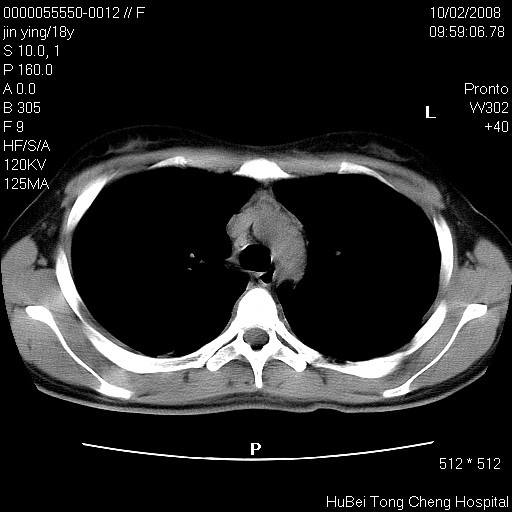

患者 女,18y。发热十余天,伴咳嗽。pe:t39⒈℃,bp 110/80mmhg,p 86次/min。神清,精神欠佳。双肺可闻及少许湿罗音。既往史不详。

临床诊断:肺部感染?

胸部ct轴位平扫(层厚10mm,螺距1.5,重建间隔10mm),图像如下: